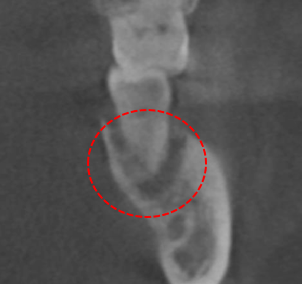

안녕하세요. 운정치과 15년 경력의 치과의사 대표원장 임희철입니다. 오늘 보시는 분들께 뿌리사랑치과에서 하셨던 분의 케이스 보여드리고 스케일링이라는 좋은 정보를 알려드리면 스케일링을 왜…